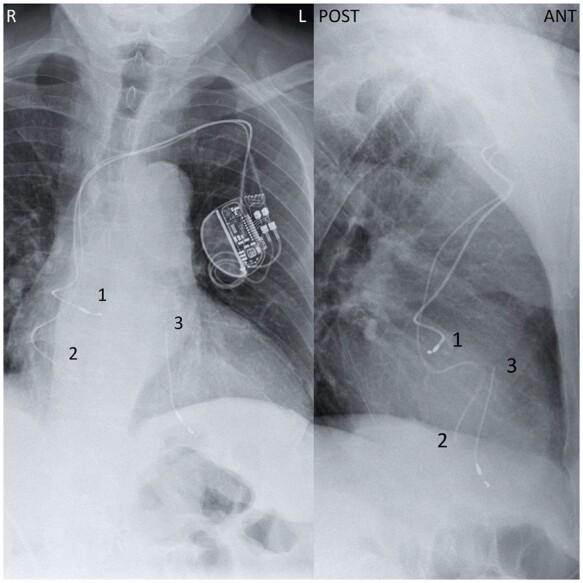

We describe the case of a 73-year-old man with a dual-chamber pacemaker presenting with subacute endocarditis and recurrent cholangitis. A few months prior, the patient was diagnosed with localized colon cancer and lead endocarditis based on nuclear imaging. He was given prolonged antibiotic therapy and lead explantation was to be performed after sigmoidectomy. During the following weeks, his condition worsened and he was readmitted for biliary sepsis. A chest X-ray revealed, incidentally, a complete ventricular lead rupture. Pacemaker electrogram showed ventricular undersensing, loss of ventricular capture, and high impedance. As his health declined, removal of the pacemaker was deemed unreasonable and the patient died of biliary sepsis in the next few weeks.

We describe the case of an asymptomatic intracardiac lead fracture in the setting of colon cancer and a medically managed lead infection. As this complication occurred during lead infection, bacterial damage may have weakened the lead over time. As illustrated by the patient's outcomes, long-term antibiotic therapy should only be used in cases unsuitable for device removal. Complete hardware removal remains the first-line therapy in patients with CIED-related infections.